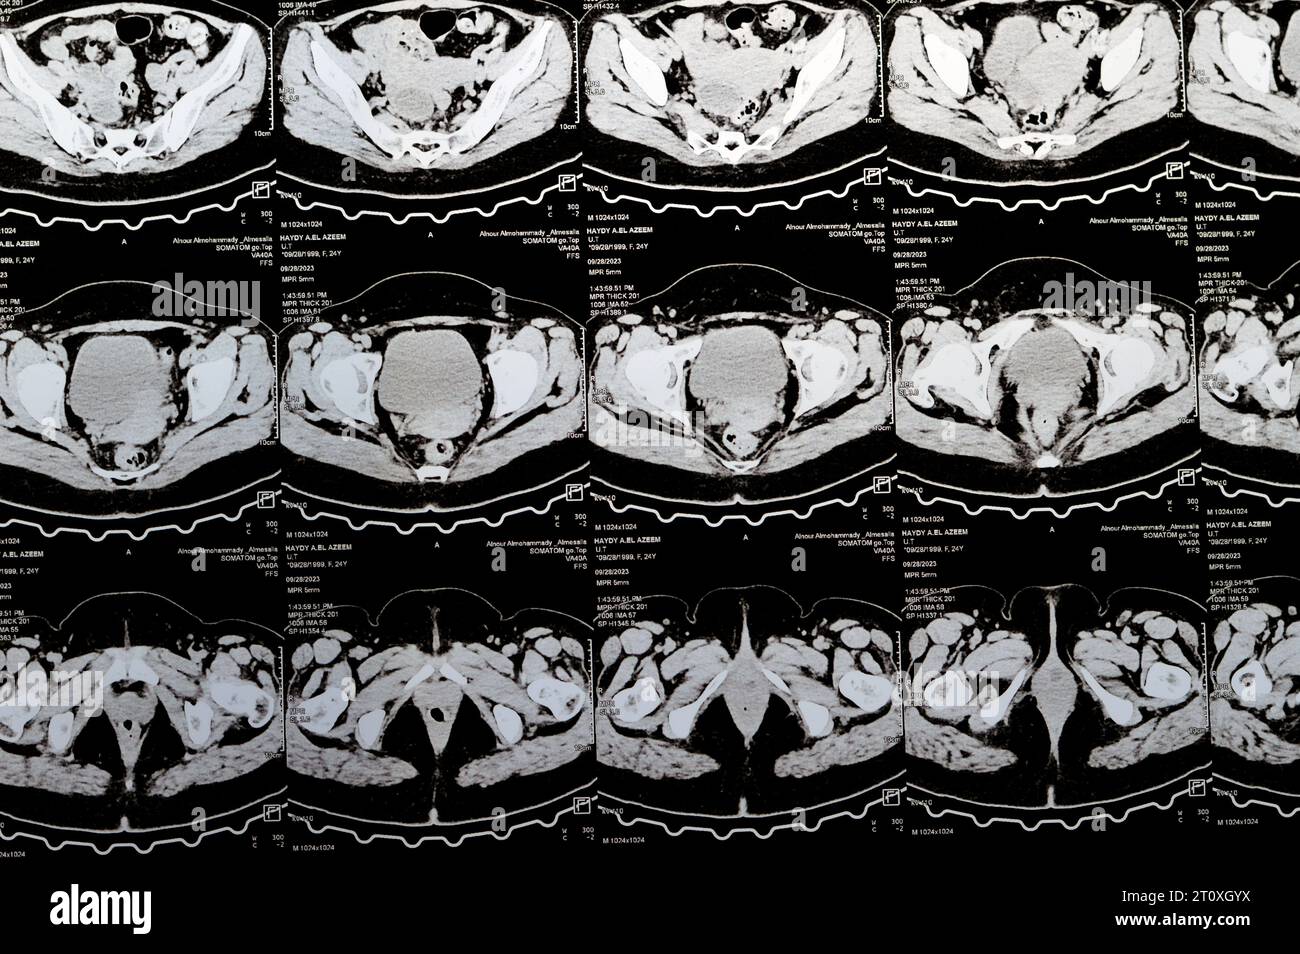

Le Caire, Égypte, octobre 3 2023 : le scanner multi-coupes de l'abdomen et du bassin montre un kyste de l'ovaire droit de 3 x 3 cm, une distension gazeuse colique, pas d'urine importante Banque D'Imageshttps://www.alamyimages.fr/image-license-details/?v=1https://www.alamyimages.fr/le-caire-egypte-octobre-3-2023-le-scanner-multi-coupes-de-l-abdomen-et-du-bassin-montre-un-kyste-de-l-ovaire-droit-de-3-x-3-cm-une-distension-gazeuse-colique-pas-d-urine-importante-image568526222.html

Le Caire, Égypte, octobre 3 2023 : le scanner multi-coupes de l'abdomen et du bassin montre un kyste de l'ovaire droit de 3 x 3 cm, une distension gazeuse colique, pas d'urine importante Banque D'Imageshttps://www.alamyimages.fr/image-license-details/?v=1https://www.alamyimages.fr/le-caire-egypte-octobre-3-2023-le-scanner-multi-coupes-de-l-abdomen-et-du-bassin-montre-un-kyste-de-l-ovaire-droit-de-3-x-3-cm-une-distension-gazeuse-colique-pas-d-urine-importante-image568526222.htmlRF2T0XGYX–Le Caire, Égypte, octobre 3 2023 : le scanner multi-coupes de l'abdomen et du bassin montre un kyste de l'ovaire droit de 3 x 3 cm, une distension gazeuse colique, pas d'urine importante

Le Caire, Égypte, octobre 3 2023 : le scanner multi-coupes de l'abdomen et du bassin montre un kyste de l'ovaire droit de 3 x 3 cm, une distension gazeuse colique, pas d'urine importante Banque D'Imageshttps://www.alamyimages.fr/image-license-details/?v=1https://www.alamyimages.fr/le-caire-egypte-octobre-3-2023-le-scanner-multi-coupes-de-l-abdomen-et-du-bassin-montre-un-kyste-de-l-ovaire-droit-de-3-x-3-cm-une-distension-gazeuse-colique-pas-d-urine-importante-image568533363.html

Le Caire, Égypte, octobre 3 2023 : le scanner multi-coupes de l'abdomen et du bassin montre un kyste de l'ovaire droit de 3 x 3 cm, une distension gazeuse colique, pas d'urine importante Banque D'Imageshttps://www.alamyimages.fr/image-license-details/?v=1https://www.alamyimages.fr/le-caire-egypte-octobre-3-2023-le-scanner-multi-coupes-de-l-abdomen-et-du-bassin-montre-un-kyste-de-l-ovaire-droit-de-3-x-3-cm-une-distension-gazeuse-colique-pas-d-urine-importante-image568533363.htmlRF2T0XX2Y–Le Caire, Égypte, octobre 3 2023 : le scanner multi-coupes de l'abdomen et du bassin montre un kyste de l'ovaire droit de 3 x 3 cm, une distension gazeuse colique, pas d'urine importante

Le Caire, Égypte, octobre 3 2023 : le scanner multi-coupes de l'abdomen et du bassin montre un kyste de l'ovaire droit de 3 x 3 cm, une distension gazeuse colique, pas d'urine importante Banque D'Imageshttps://www.alamyimages.fr/image-license-details/?v=1https://www.alamyimages.fr/le-caire-egypte-octobre-3-2023-le-scanner-multi-coupes-de-l-abdomen-et-du-bassin-montre-un-kyste-de-l-ovaire-droit-de-3-x-3-cm-une-distension-gazeuse-colique-pas-d-urine-importante-image568532396.html

Le Caire, Égypte, octobre 3 2023 : le scanner multi-coupes de l'abdomen et du bassin montre un kyste de l'ovaire droit de 3 x 3 cm, une distension gazeuse colique, pas d'urine importante Banque D'Imageshttps://www.alamyimages.fr/image-license-details/?v=1https://www.alamyimages.fr/le-caire-egypte-octobre-3-2023-le-scanner-multi-coupes-de-l-abdomen-et-du-bassin-montre-un-kyste-de-l-ovaire-droit-de-3-x-3-cm-une-distension-gazeuse-colique-pas-d-urine-importante-image568532396.htmlRF2T0XTTC–Le Caire, Égypte, octobre 3 2023 : le scanner multi-coupes de l'abdomen et du bassin montre un kyste de l'ovaire droit de 3 x 3 cm, une distension gazeuse colique, pas d'urine importante

Le Caire, Égypte, octobre 3 2023 : le scanner multi-coupes de l'abdomen et du bassin montre un kyste de l'ovaire droit de 3 x 3 cm, une distension gazeuse colique, pas d'urine importante Banque D'Imageshttps://www.alamyimages.fr/image-license-details/?v=1https://www.alamyimages.fr/le-caire-egypte-octobre-3-2023-le-scanner-multi-coupes-de-l-abdomen-et-du-bassin-montre-un-kyste-de-l-ovaire-droit-de-3-x-3-cm-une-distension-gazeuse-colique-pas-d-urine-importante-image568507925.html

Le Caire, Égypte, octobre 3 2023 : le scanner multi-coupes de l'abdomen et du bassin montre un kyste de l'ovaire droit de 3 x 3 cm, une distension gazeuse colique, pas d'urine importante Banque D'Imageshttps://www.alamyimages.fr/image-license-details/?v=1https://www.alamyimages.fr/le-caire-egypte-octobre-3-2023-le-scanner-multi-coupes-de-l-abdomen-et-du-bassin-montre-un-kyste-de-l-ovaire-droit-de-3-x-3-cm-une-distension-gazeuse-colique-pas-d-urine-importante-image568507925.htmlRF2T0WNJD–Le Caire, Égypte, octobre 3 2023 : le scanner multi-coupes de l'abdomen et du bassin montre un kyste de l'ovaire droit de 3 x 3 cm, une distension gazeuse colique, pas d'urine importante